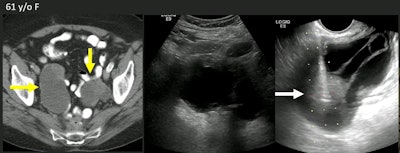

Maintaining viable tissue at the site of disease is important for tailoring treatment decisions. The complex anatomy of the pelvic region can make determining the best treatment options for women with pelvic lesions tricky. TVUS shows promise for offering better staging for deep pelvic targets for access without disturbing vulnerable structures. Lubner noted that there are previous studies assessing TVUS biopsy, but he added that data on core biopsies are lacking.

The researchers found that a TVUS-guided approach significantly decreased the distance to the biopsy target by an average of 10.7 mm; transabdominal ultrasound had an average distance to biopsy target of 86 mm (p < 0.0001).

Also, the average lesion size on TVUS was 40 mm. Targets at or above the vaginal cuff and up to above the acetabular roof were also accessible.

"One of the potential advantages of transvaginal ultrasound is that it really has great resolution for identifying solid components that we can target for biopsy," she said.